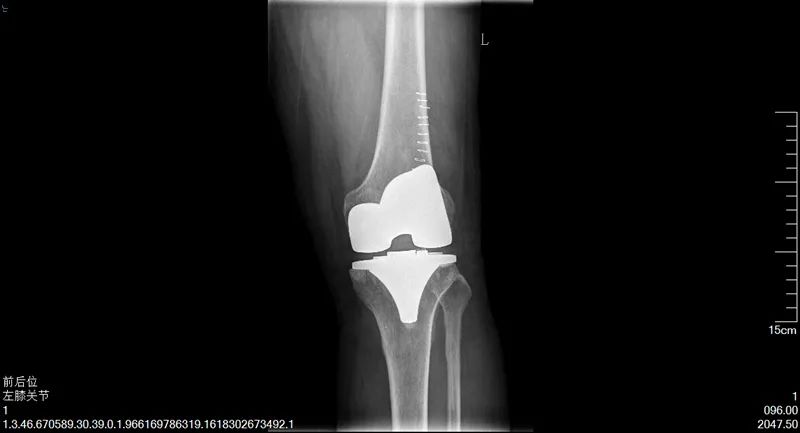

陳阿姨的故事,說來還要將時間追溯至十年前,陳阿姨常年操持家中的生意,雙膝落下了問題,時常疼痛難忍,后來甚至發(fā)展至不能正常行走。這時,鄰居常大哥告訴她,可以試試到市第一人民醫(yī)院看看。隨即,陳阿姨來到了我院骨科二病區(qū)找到了楊勇主任,做了雙側(cè)人工全膝關(guān)節(jié)置換術(shù),術(shù)后恢復(fù)得非常好,雙腿和正常人無異,既不疼了,也能站直了。時至今日,陳阿姨說她的腿依然健康如初,每天可以去跳廣場舞,生活質(zhì)量得到了顯著提高。

手術(shù)后

同時聽陳阿姨介紹,鄰居常大哥也是因患有類風(fēng)濕性關(guān)節(jié)炎,雙膝關(guān)節(jié)屈曲,不能伸直,疼痛不能行走,病情比陳阿姨更為嚴(yán)重,經(jīng)楊主任手術(shù)后,雙腿恢復(fù)正常,生活質(zhì)量大大提高。